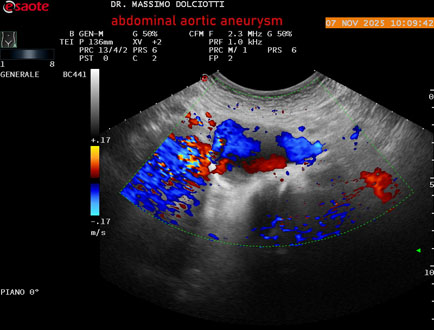

Data inserimento: 11/11/2025

Ecografia del: 07/11/2025

Strumento: Esaote MyLab Eight

Sonda: Convex Multifrequenza 1-8 MHz

Età Paziente: M 60 anni

Motivazione dell'esame: follow up per aneurisma dell'aorta addominale.

Commento all'esame: le immagini ed il video documentano la presenza dell'aneurisma dell'aorta addominale sotto-renale, con diametro antero-posteriore massimo documentato di 47 / 48 mm.

Conclusioni: aneurisma dell'aorta addominale in follow up (abdominal aortic aneurysm follow-up).

Presentazione: Dr. Massimo Dolciotti - Ancona